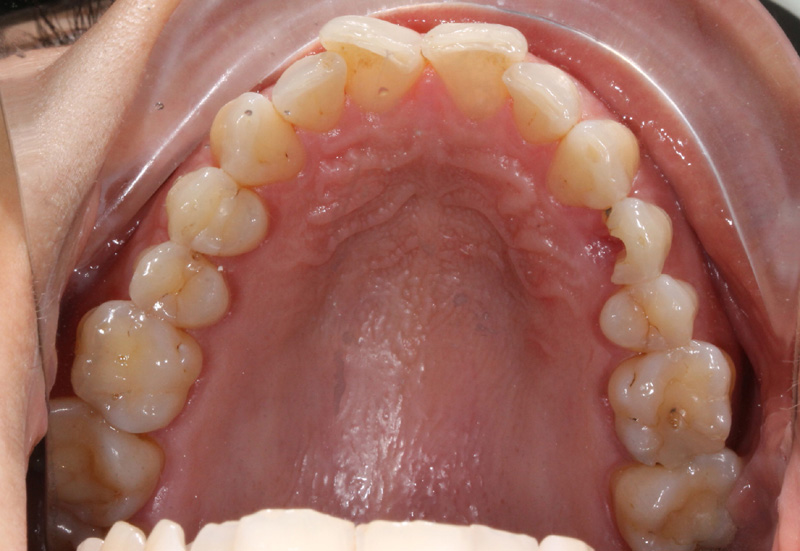

La paziente si presenta alla nostra osservazione con una frattura verticale di un primo premolare superiore.

L'impianto inserito dopo l'estrazione è un Starumann Tapered Effect di 4,1 mm di diametro e 12 mm di lunghezza.